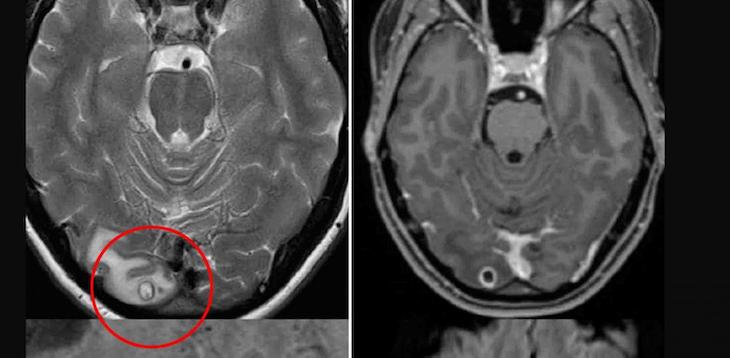

Врачи были убеждены в том, что у девушки рак. Однако опухолью оказалось скопление личинок ленточного червя.

Девушке поставили диагноз нейроцистицеркоз — заражение свиным цепнем. Данный диагноз вызвал много вопросов. В это не могли поверить не только местные специалисты, но также медики, которые занимаются тропической медициной.

Причиной стало то, что в Австралии заразиться им невозможно, а пациентка никогда не покидала пределы страны. От ленточных червей, как правило, страдают жители Латинской Америки, Юго-Восточной Азии и Африки.